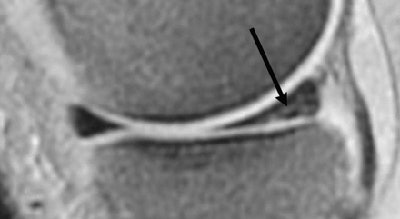

| Conventional spin-echo versus fast spin-echo imaging for detection of meniscal tear in 50-year-old woman. Sagittal conventional spin-echo proton density-weighted MR image (TR/TE, 2,000/20) with fat suppression obtained through medial meniscus shows complex tear of posterior horn (arrow). |

![]() |

| Conventional spin-echo versus fast spin-echo imaging for detection of meniscal tear in 50-year-old woman. Sagittal fast spin-echo proton density-weighted MR image (3,000/17) with fat suppression obtained through medial meniscus does not show meniscal tear. Garyun BB, Major NM, Helms CA, "Comparison of Fast Spin-Echo Versus Conventional Spin-Echo MRI for Evaluating Meniscal Tears" (AJR 2005; 184:1740-1743). |